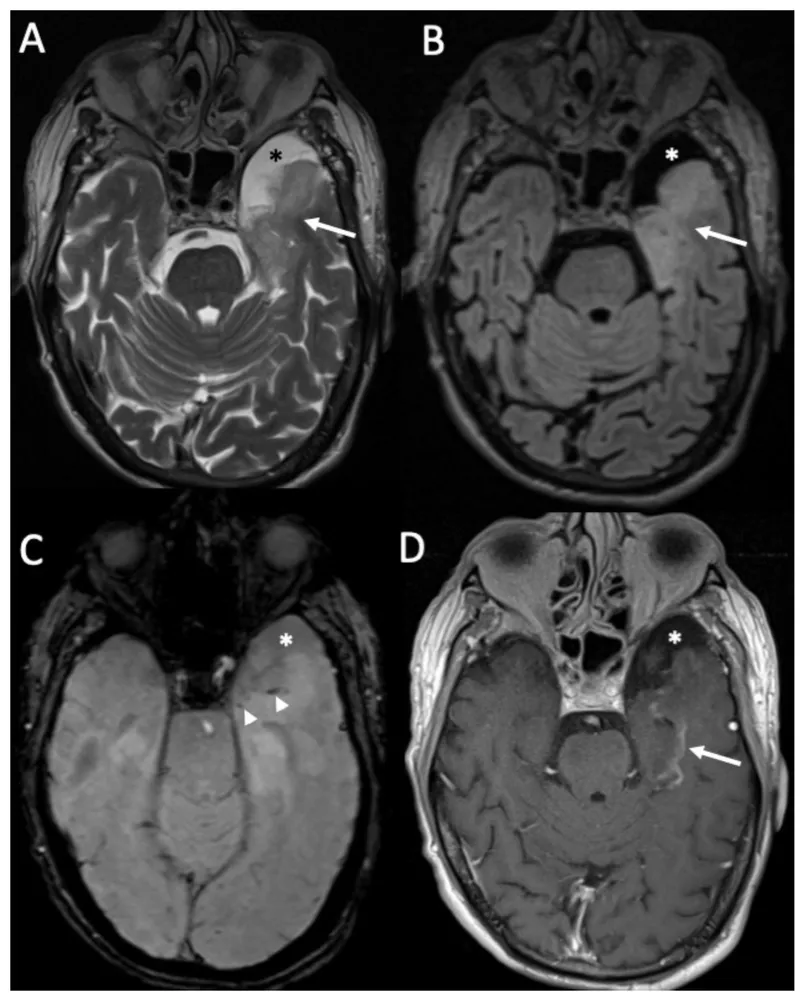

- Lesion: Bilateral amygdala damage (e.g., HSV-1 encephalitis, trauma).

⭐ Herpes Simplex Virus-1 (HSV-1) Encephalitis classically targets the medial temporal lobes and inferior frontal lobes, leading to acute hemorrhagic necrosis and severe neurological sequelae.